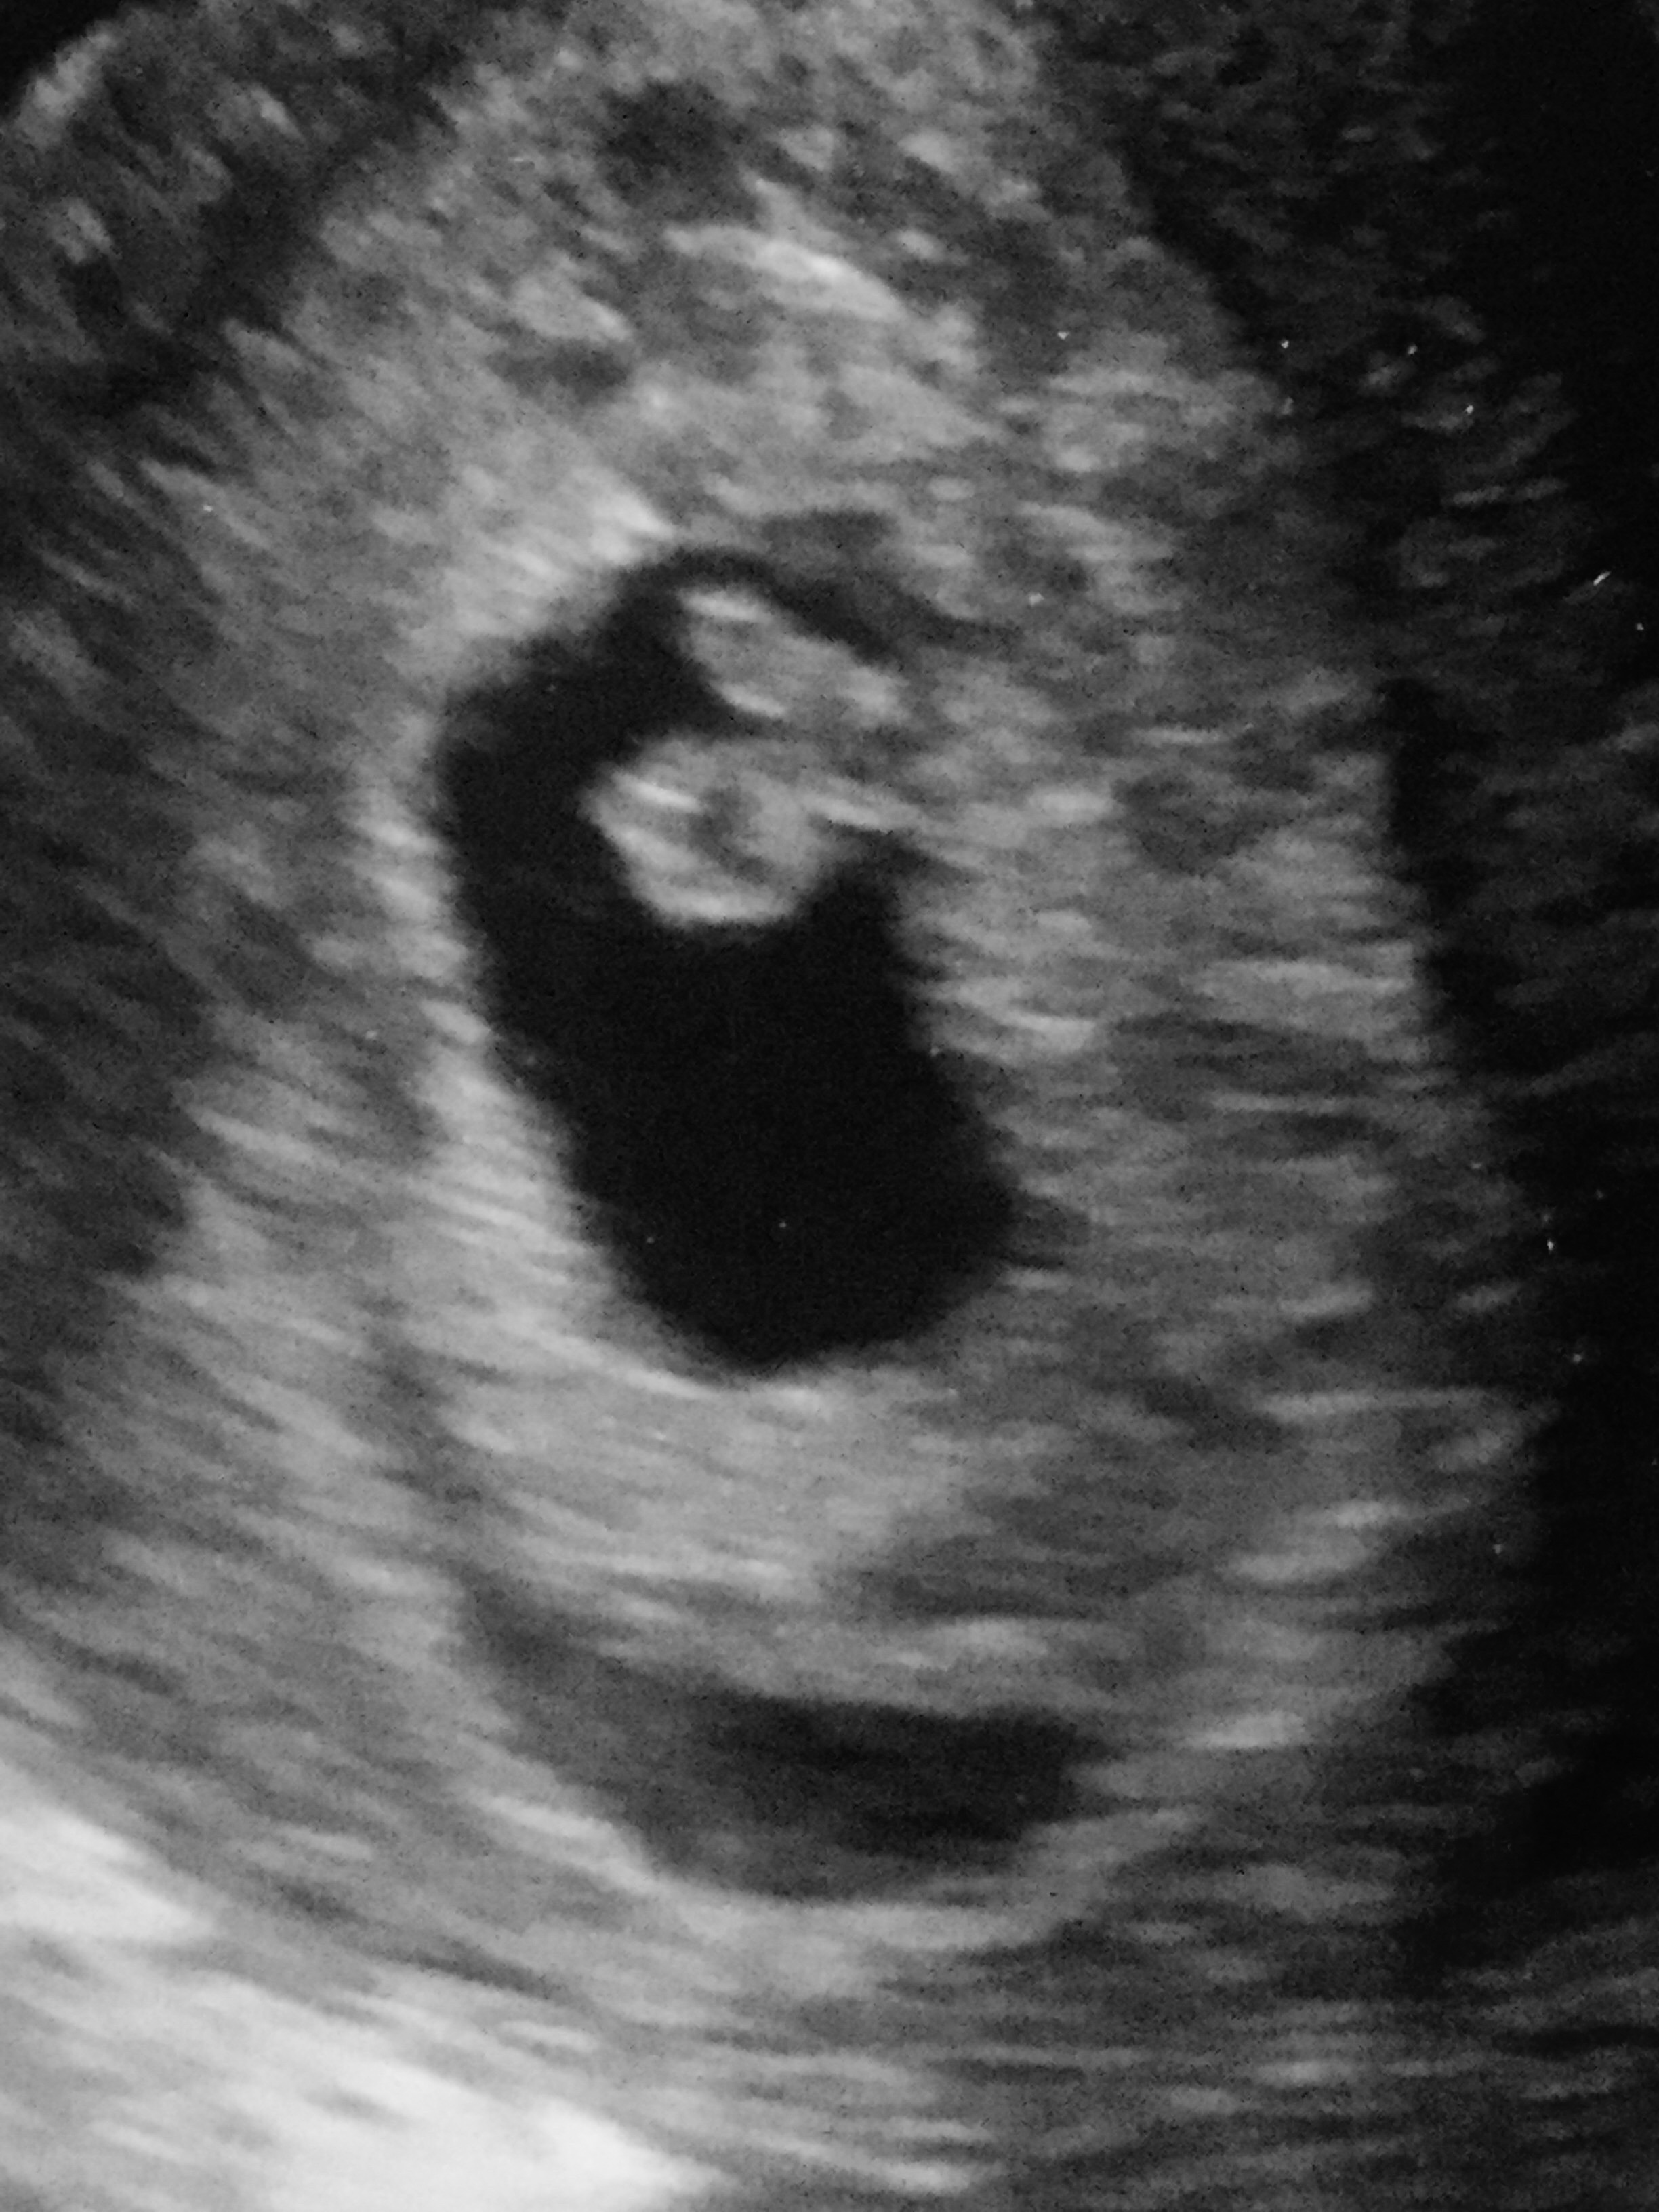

Hi, I am 8 wk preggo. I had bleeding I went to the er and bleeding stop but still spotting. I went back to home and still spotting. Wonder how long it will stop spotting or high risk possible miscarriage? I had little but cramp but only brief time and no pain. Should I be concern?